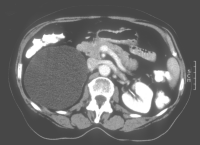

Die Patientin wurde beim Urologen wegen seit 3 Wochen persistierender Flankenschmerzen rechts vorstellig. Der Untersuchungsbefund zeigte als Auffälligkeit ein klopf- und druckschmerzhaftes Nierenlager rechts. Der Urinstatus wies keine Besonderheiten auf. Sonographisch fand der Urologe eine ca. 11 cm große einfache Nierenzyste rechts, die bis in das Nierenbecken reichte. Mit dem anschließend durchgeführten i.v.-Pyelogramm konnte eine Abflussbehinderung aus dem Nierenhohlraumsystem ausgeschlossen werden. Es waren jedoch glatt berandete, zystentypische Kelchausziehungen der oberen und mittleren Kelchgruppe zu erkennen. Der Urologe stellte die Patientin stationär in der Klinik vor. Zum Ausschluss eines eventuell vorliegenden zystischen Karzinoms wurde ein CT des Abdomens durchgeführt. Hier fand sich eine große, unkomplizierte Zyste, die die Niere verdrängte (Abbildung 4).